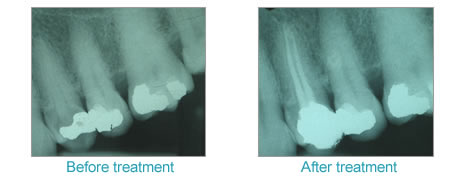

This, along with the use of digital X-rays to reduce your exposure by 90% compared to old film X-rays, ensures you receive safe and reliable treatment.